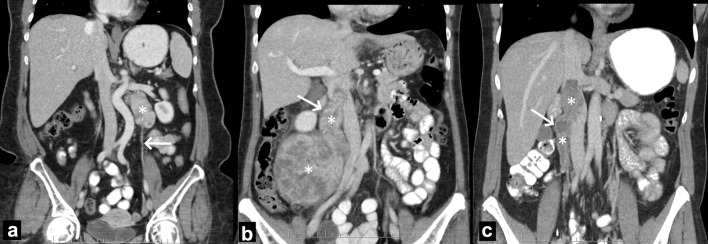

Methods: A retrospective review of imaging of all patients presenting with abdominal non-uterine LMS at a single tertiary oncology center was performed. Inclusion criteria were a biopsy-proven LMS of non-uterine abdominal/pelvic origin with pretreatment enhanced computed tomography (CT)/magnetic resonance imaging (MRI). Patients with uterine LMS or prior radiation were excluded. LMS site of origin was assigned by one expert radiologist and indeterminate sites were reviewed with a second external expert radiologist. Locations of inferior vena cava (IVC) tumors were subclassified based on a modification of prior literature. SHDP was defined as originating from ovarian/testicular vein, distal left renal vein, adrenal vein or mid-IVC (IIA).

Results: One hundred fifty-five (155) patients were included (92/152 (61%) female) with distant metastases found at presentation in 23/155 (14.8%). Most common organs of origins were veins (84/152, 55.3%), gastrointestinal (24, 15.8%), genital (11, 7.2%) and paratesticular/spermatic cord (11, 7.2%). For venous LMS, the adrenal (both sexes), mid-IVC (IVC IIA, females) and ovarian veins had the highest relative predilection for abdominal non-uterine LMS. Eighty-four (84/152, 55.3%) of tumors were SHDP. On multivariable analysis, both size and SHDP were significant predictors of distant metastases at presentation (P = 0.01), while sex, age, organ system/site and grade were not.